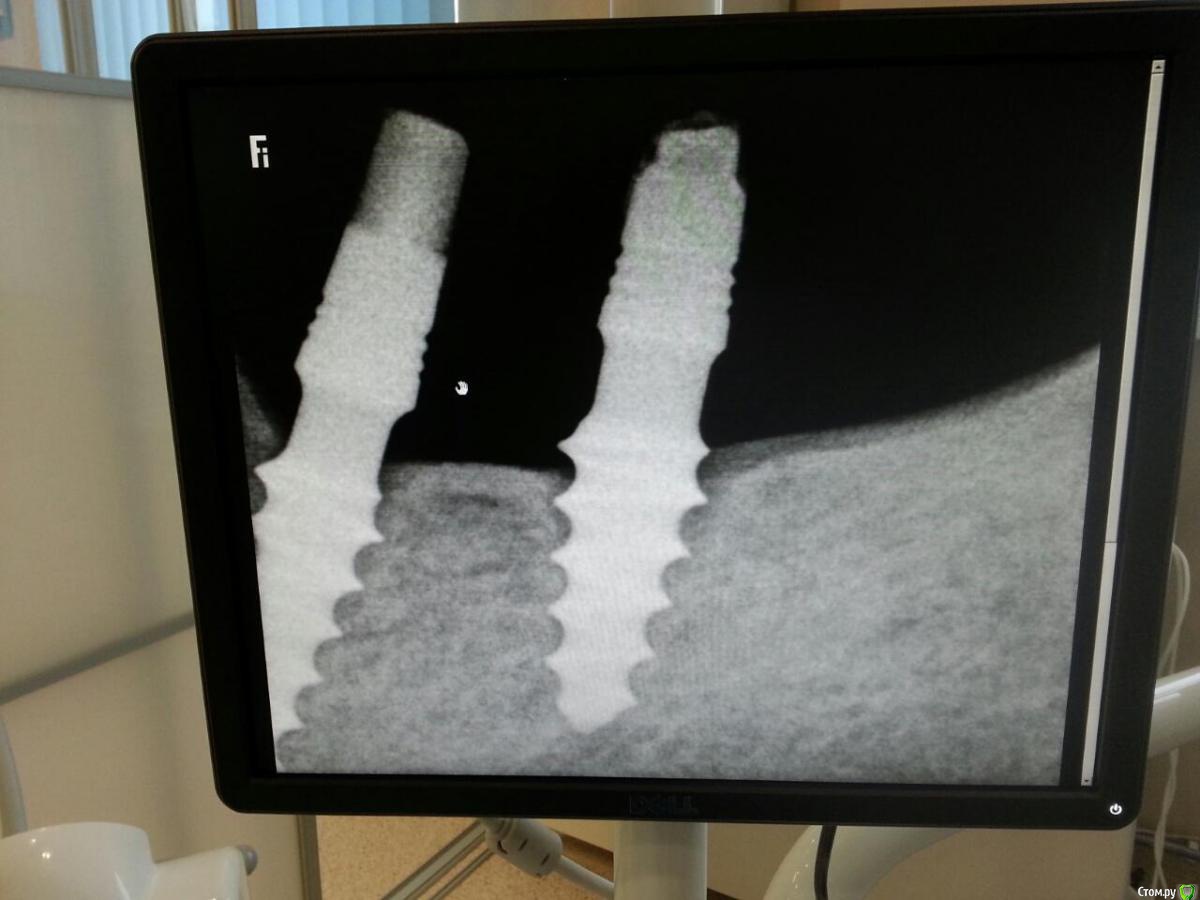

dok1 Опубликовано 4 марта, 2016 Поделиться Опубликовано 4 марта, 2016 Автор не я. Не устанавливал ни разу. Коллега попросил проконсультировать. Вводная: длина интегрированной части 8 или 9 мм, не более, ширина гребня достаточная для классических имплантов. Установлены несколько месяцев назад. Временные коронки присутствуют, вроде конструкция устойчива. Носитель мужчина средних лет нормального телосложения. проэкция 6 и 7 н.ч. Выбор хирурга в пользу данных имплантов (со слов коллеги, хирург тоже не он) сделан по требованиям пациента - быстро, малоинвазивно. Коллеге предстоит протезировать, он опасается. Интересно мнение бывалых. Вопрос: долгосрочен ли проэкт, не велика ли нагрузка жевательного отдела? Ссылка на комментарий

Доктор Добрых Дел Опубликовано 5 марта, 2016 Поделиться Опубликовано 5 марта, 2016 Там по-моему уже периимплантит. Я бы выкрутил и поставил нормальные винты. Ссылка на комментарий

dok1 Опубликовано 5 марта, 2016 Автор Поделиться Опубликовано 5 марта, 2016 Да я тоже за нормальные винты. Периимплантита чётко не увидел, но интеграция слабовата показалась. Ссылка на комментарий